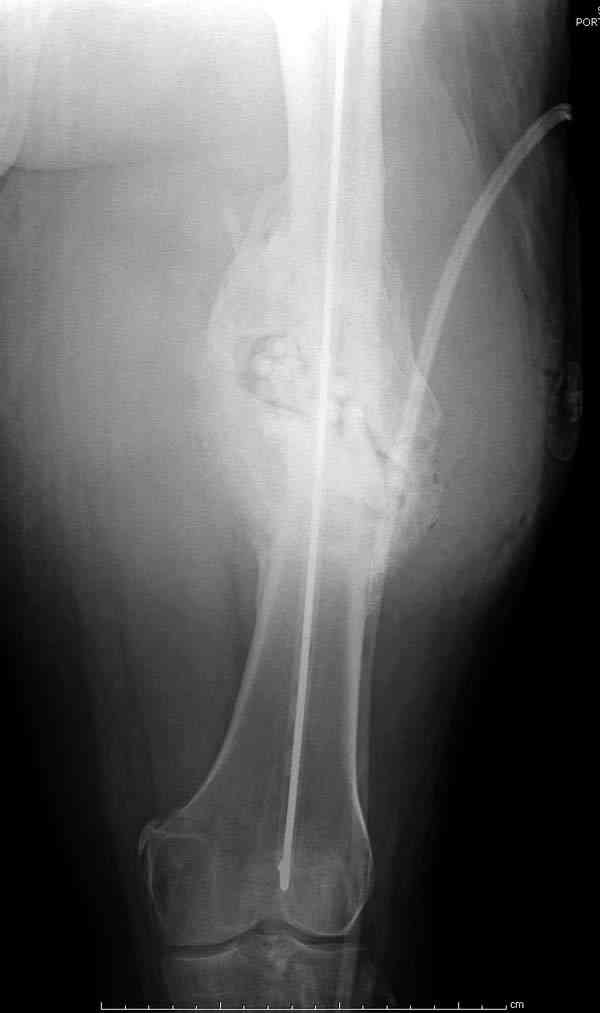

На ренгенограмме явный остеомиелит с секвестром, секвестерэктомия из медиального доступа и замена старого антибиотического гвоздя на новый.

После трех дней ваккуумного дренажа, из латерального доступа удаление остатков старых антибиотичеких бус, закрытие медиальной раны с наложением ваккуумирования латерально. В следующий раз, через пару дней надеемся закрыть рану.